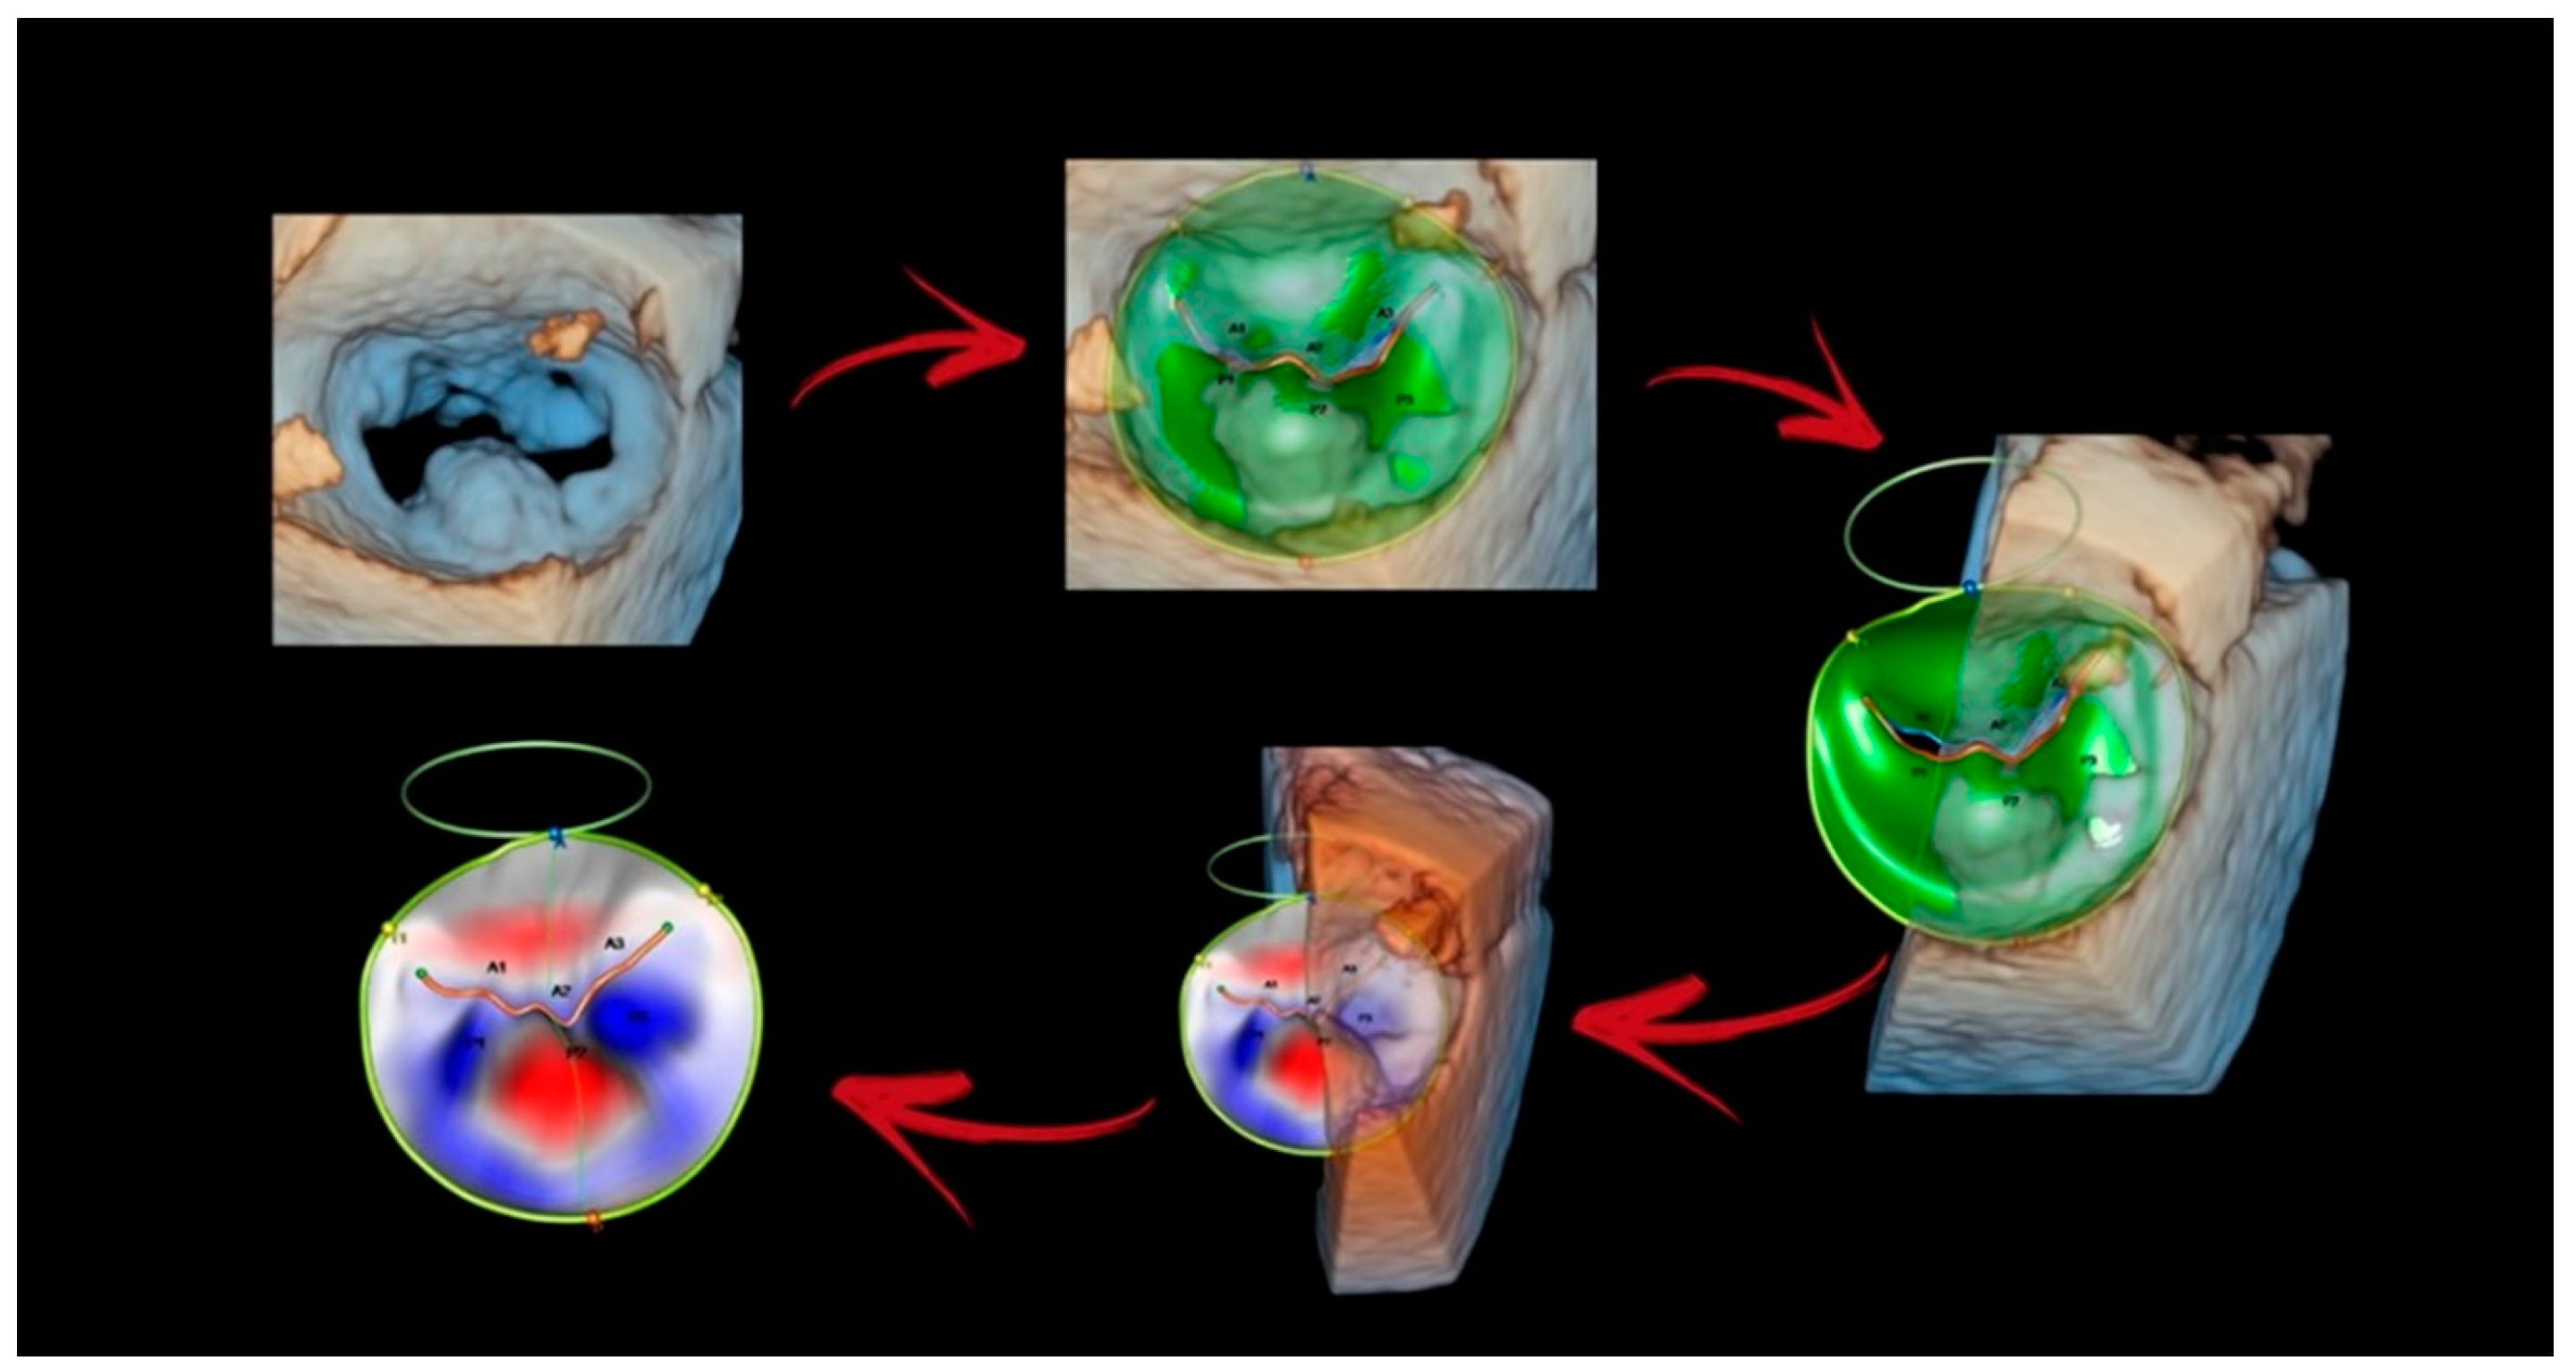

4.1. Photorealistic Vision and Transparency

4.2. Surface Rendering